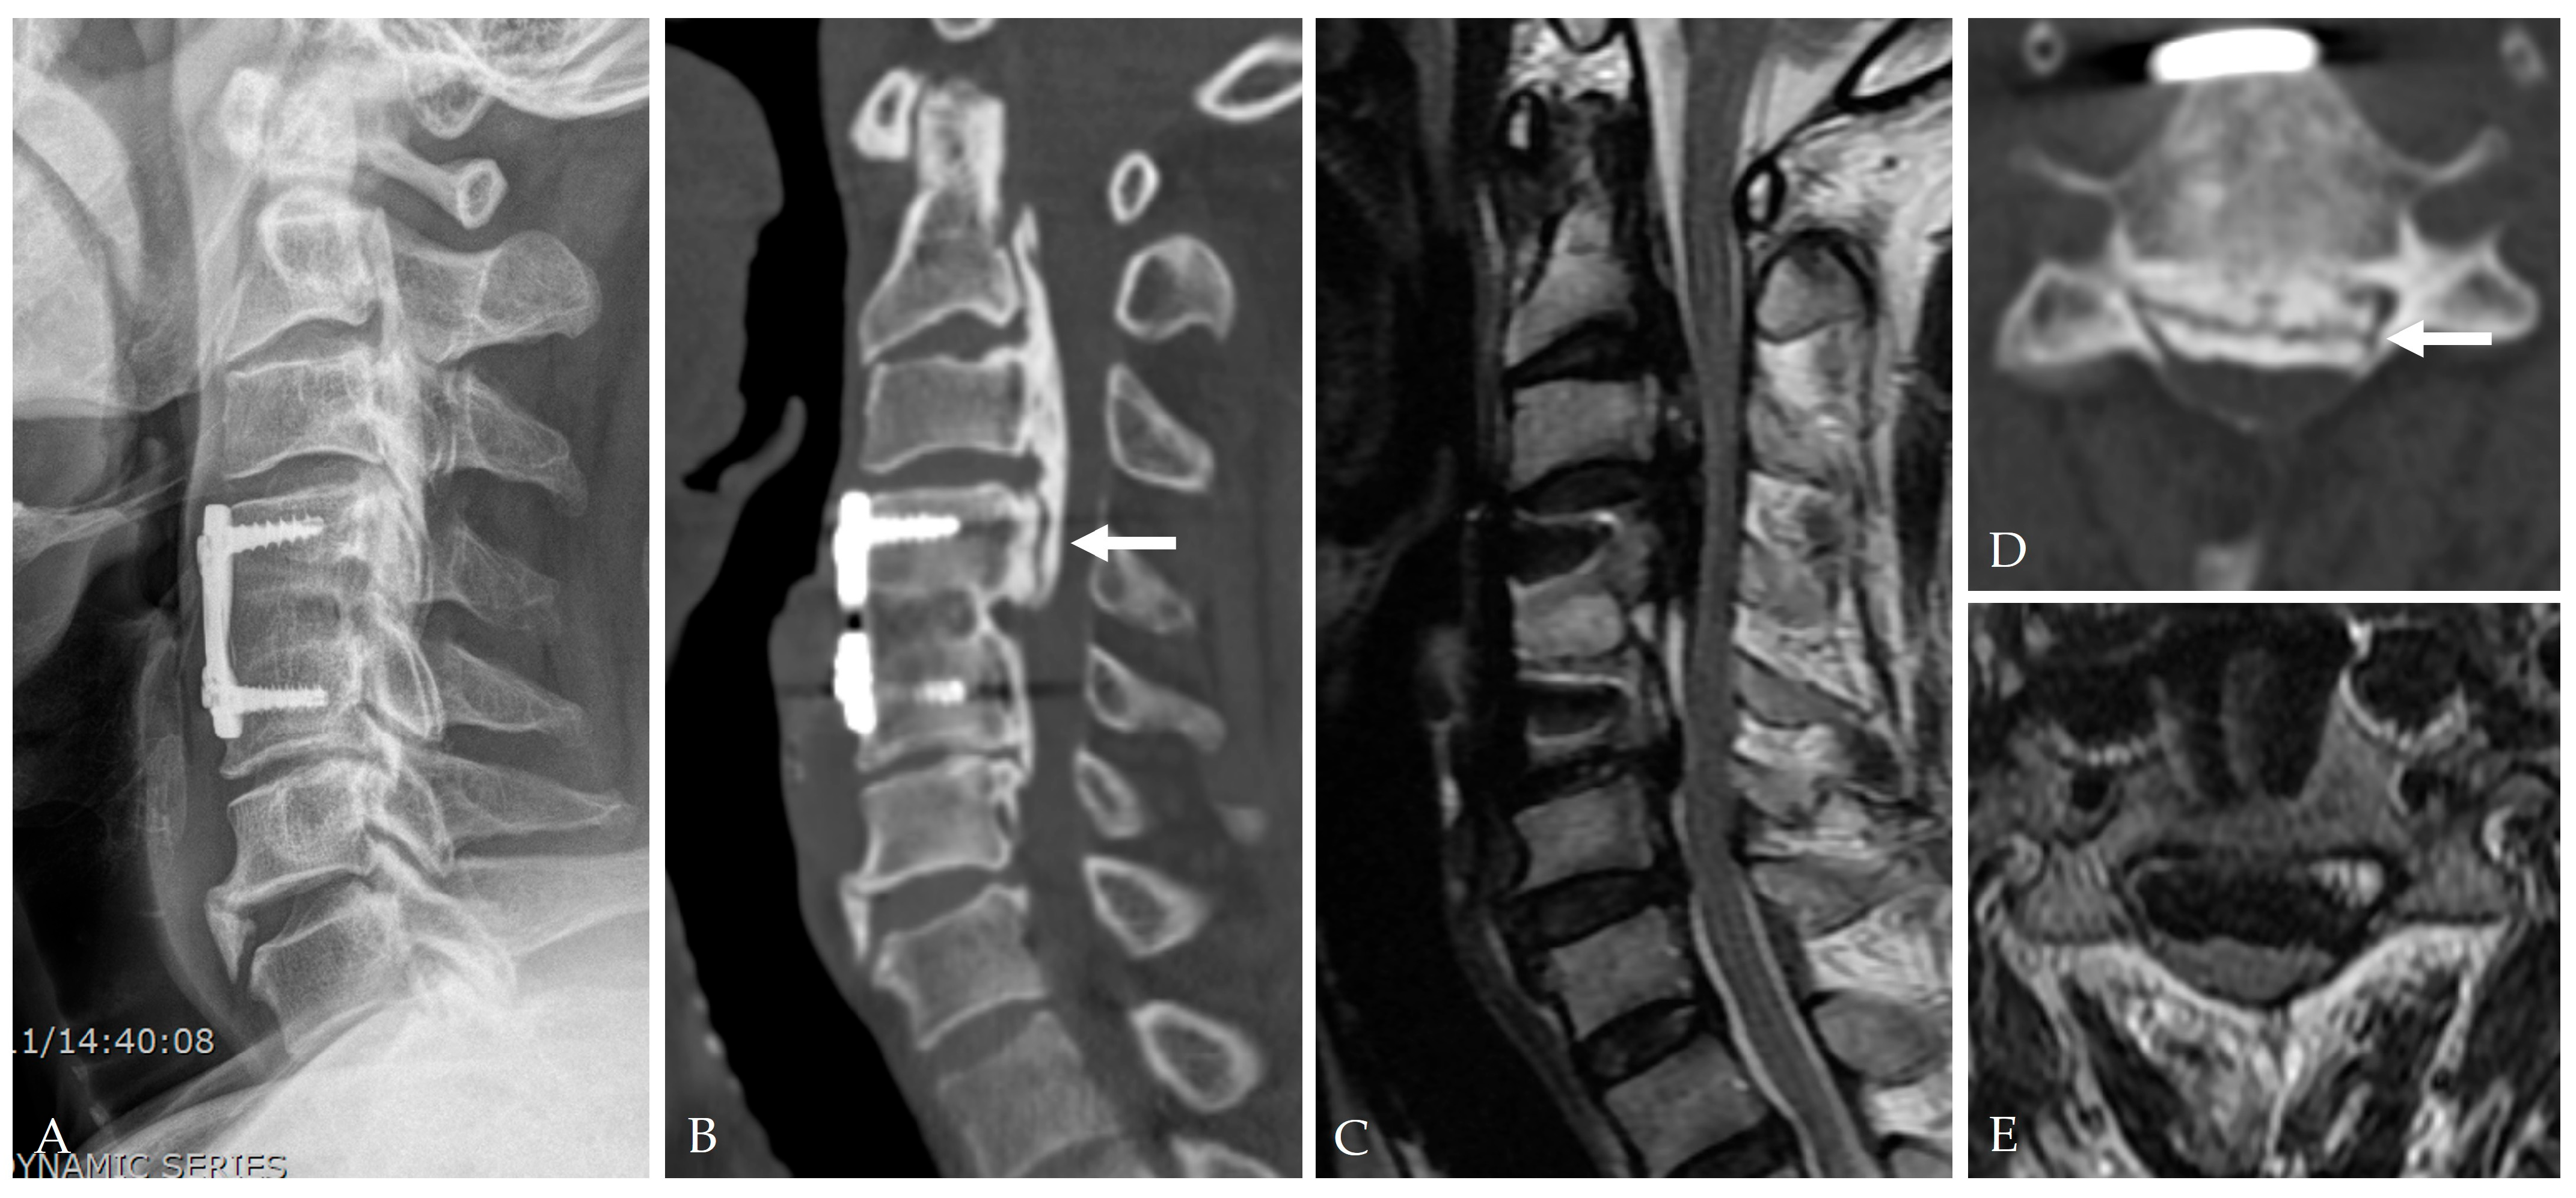

2.4. Radiologic Predictors and Morphological Correlates

- Broad-based or continuous/mixed-type OPLL: Confers approximately 10-fold higher risk of DT than segmental types [37].

2.5. Disease-Specific Factors: Dural Ossification and Adhesion Severity

- Min, J.H.; Jang, J.S.; Lee, S.H. Clinical significance of the double-layer sign on computed tomography in OPLL. Neurosurgery 2007, 61, 118–121. [Google Scholar] [CrossRef]

- Yang, H.; Yang, L.; Chen, D.; Wang, X.; Lu, X.; Yuan, W. Implications of different patterns of the “double-layer sign” in cervical OPLL. Eur. Spine J. 2015, 24, 1631–1639. [Google Scholar] [CrossRef]

- Chen, Y.; Guo, Y.; Chen, D.; Lu, X.; Wang, X.; Tian, H.; Yuan, W. Diagnosis and surgery of OPLL associated with dural ossification in the cervical spine. Eur. Spine J. 2009, 18, 1541–1547. [Google Scholar] [CrossRef]

- Epstein, N.E. Identification of OPLL extending through the dura on preoperative CT of the cervical spine. Spine 2002, 27, 182–186. [Google Scholar]

- Mizuno, J. Radiologic evaluation of ossification of the posterior longitudinal ligament with dural ossification. Neurosurg. Clin. N. Am. 2018, 29, 55–61. [Google Scholar] [CrossRef] [PubMed]